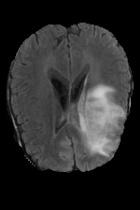

Current unsupervised anomaly localization approaches rely on generative models to learn the distribution of normal images, which is later used to identify potential anomalous regions derived from errors on the reconstructed images. However, a main limitation of nearly all prior literature is the need of employing anomalous images to set a class-specific threshold to locate the anomalies. This limits their usability in realistic scenarios, where only normal data is typically accessible. Despite this major drawback, only a handful of works have addressed this limitation, by integrating supervision on attention maps during training. In this work, we propose a novel formulation that does not require accessing images with abnormalities to define the threshold. Furthermore, and in contrast to very recent work, the proposed constraint is formulated in a more principled manner, leveraging well-known knowledge in constrained optimization. In particular, the equality constraint on the attention maps in prior work is replaced by an inequality constraint, which allows more flexibility. In addition, to address the limitations of penalty-based functions we employ an extension of the popular log-barrier methods to handle the constraint. Comprehensive experiments on the popular BRATS'19 dataset demonstrate that the proposed approach substantially outperforms relevant literature, establishing new state-of-the-art results for unsupervised lesion segmentation.